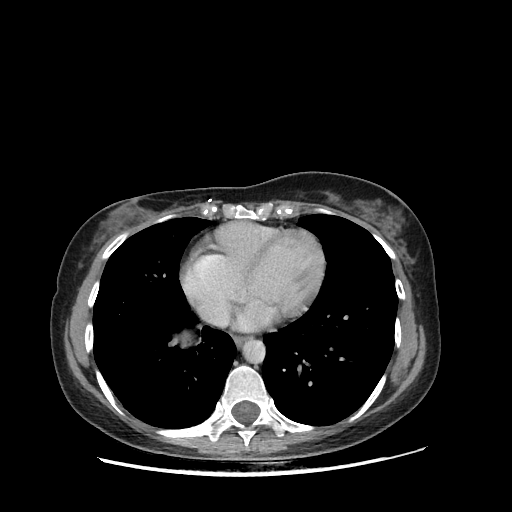

Image Grid

4Γ—3 grid: Rows show different image types (Original NATIVE, Reconstructed NATIVE, Original VENOUS, Generated VENOUS), Columns show windowing techniques (No Window, Lung Window, Mediastinum Window)

Generated VENOUS CT scan (A→B translation)

Full window (WL 1023.5, WW 4095 β†’ Low βˆ’1024, High +3071)